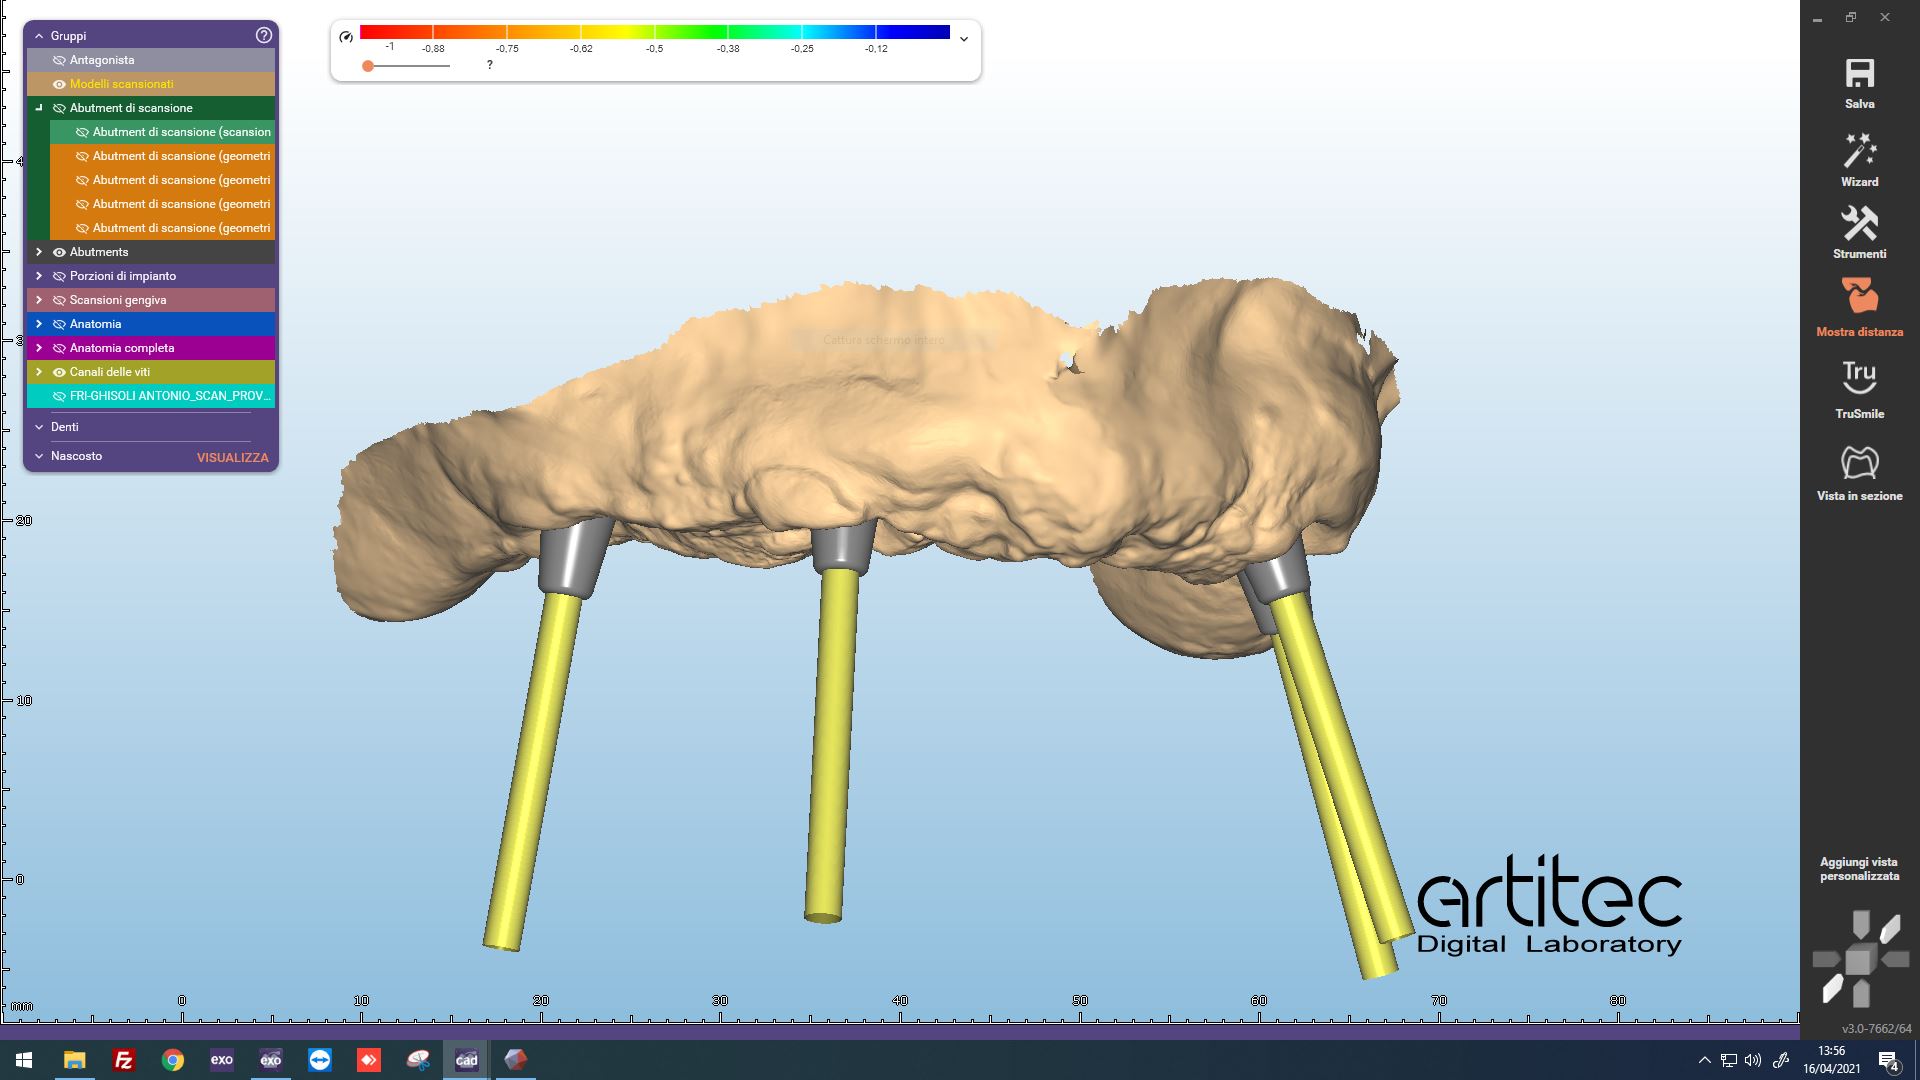

Fig. 3 Abutment virtuali posizionati

Fig. 4 Allineamento con librerie implantari virtuali